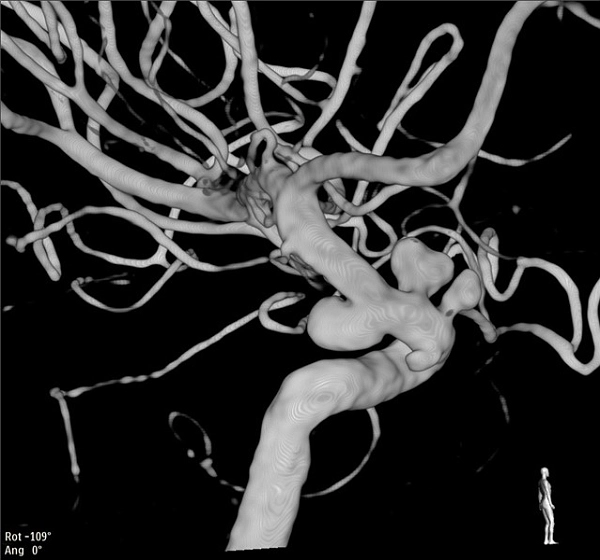

Nový dvourovinný angiografický systém během výkonu. Foto: Krajská zdravotní

Nový dvourovinný angiografický systém je určen především pro komplexní neurointervenční výkony, zejména v oblasti cévních onemocnění mozku. Přístroj umožňuje rychlé, přesné a bezpečné zákroky s důrazem na maximální ochranu pacienta i zdravotnického personálu před radiační zátěží. Významným přínosem je nově i možnost neinvazivně vyšetřovat pacienty po léčebných zákrocích, bez nutnosti další hospitalizace.